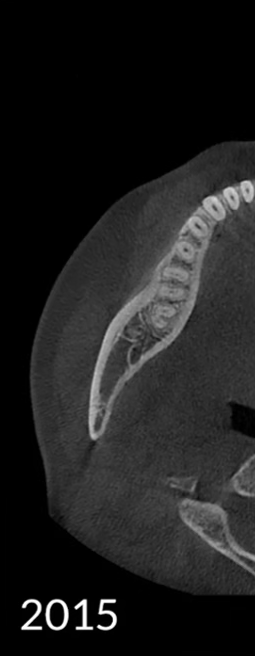

Các hiện vật kim loại được xóa bằng công nghệ AI và cấu trúc răng, mão kim loại và cấy ghép được phục hồi chính xác dựa trên các nguyên tắc toán học.

Không có MAR

MAR cũ

MAR mới